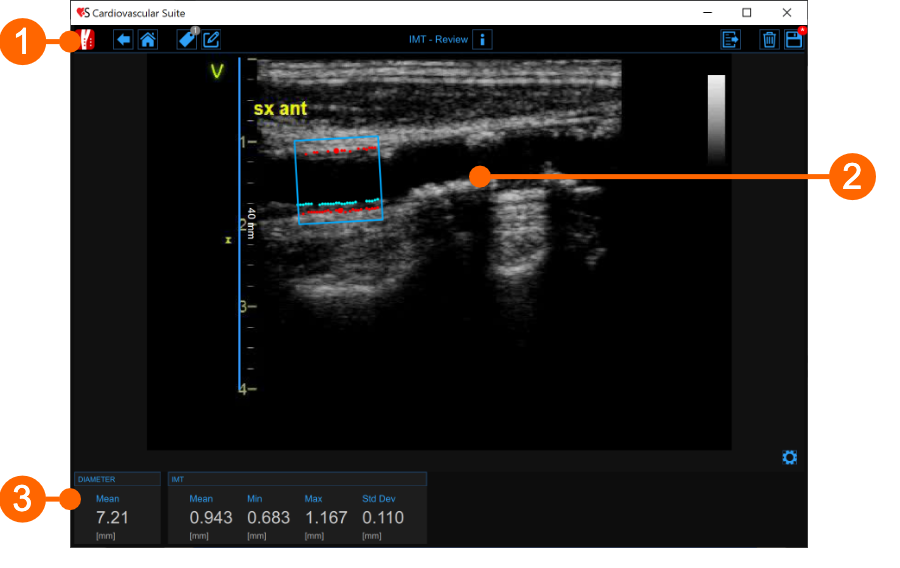

The Review window contains the following components:

1. Top bar

2. Image window

The image window shows the media file that has been analysed. It shows also the ROI and the calibration line used.

3. Results panel

The panel shows the results of the analysis. The following data are displayed:

• Mean diameter [mm]: value of the average diameter. It is computed as an average value of the data present in the ROI.

• Mean IMT [mm] Intima Media Thickness. It is computed as an average value of the data present in the ROI.

• Minimum IMT [mm] minimum value of Intima Media Thickness. It is computed on the data present in the ROI.

• Maximum IMT [mm] maximum value of Intima Media Thickness. It is computed on the data present in the ROI.

• Std. dev IMT [mm]: standard deviation of Intima Media Thickness. It is computed on the data present in the ROI.